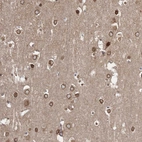

Immunohistochemistry analysis in human testis and pancreas tissues using HPA034521 antibody. Corresponding PRC1 RNA-seq data are presented for the same tissues.